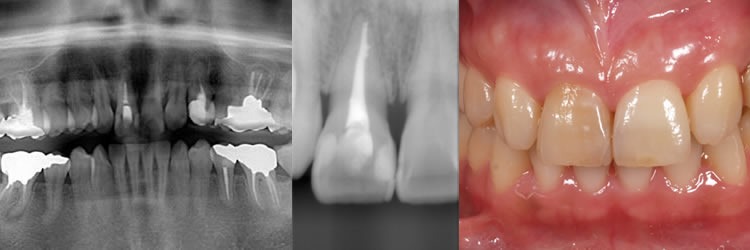

歯の内部にヒビが入った前歯

初診時